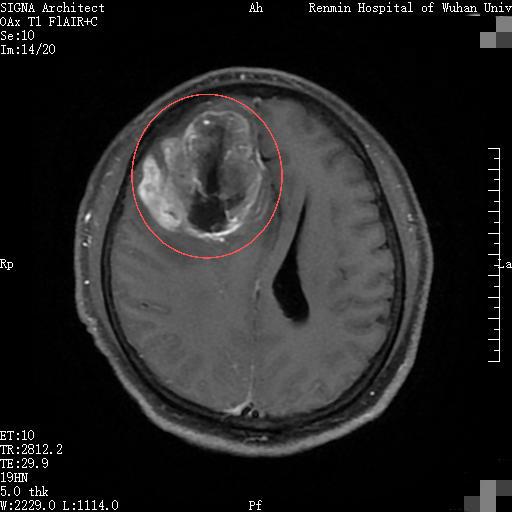

一月前,湖北黄石市民李先生因持续半个月出现全身乏力、精神萎靡等症状,来到武汉大学人民医院东院区就诊。入住风湿免疫科后,颅脑核磁共振检查显示,其右侧额叶有一6cm×5.5cm巨大占位,高度怀疑为恶性肿瘤,且肿瘤已侵犯胼胝体并累及左侧额叶。

更危急的是,巨大肿瘤引发严重脑水肿,导致大脑镰下疝、额叶直回疝形成,鞍上池受压变形,还伴有脑积水。此时,李先生颅内状况如同一颗被挤到极限的“炸弹”,随时可能危及生命。

术中可见肿瘤体积巨大,血供异常丰富,与周围水肿的脑组织边界模糊,且已跨越中线,手术难度极大。王峻教授团队如“雕刻”般进行操作,彻底切除病变组织,同时小心翼翼保护负责运动、语言等重要功能的脑区及关键血管。术后,患者受压移位的脑组织逐渐复位,颅内生命通道恢复通畅。影像学复查结果显示,肿瘤切除效果满意,脑疝完全复位。